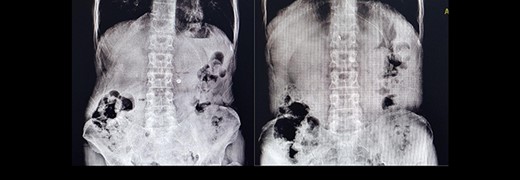

A 60-year-old male presented to the emergency department complaining of epigastric pain, recurrent hematemesis and coffee-ground vomiting for 3 days. He did not have any history of melena and weight loss. Twelve years earlier, he had undergone distal gastrectomy with vagotomy due to a noncancerous peptic ulcer. He had the endoscopic result with him, which reported gastric tumor with bleeding and obstruction in the gastrojejunostomy site. In physical examination, he was pale and ill. The blood pressure was 80/60 mm Hg, pulse rate at 110 bpm, respiratory rate of 25 per min and he had a temperature of 37°C. In abdominal examination, midline abdominal scar of a previous laparotomy was noted. He had moderate to severe tenderness of epigastric region without guarding, and a mild generalized tenderness without rebound tenderness or mass-like lesion. Bowel sounds and rectal examination were normal. According to our findings, we suspected a gastric tumor as the main cause, and we requested a repeat of endoscopy. Also, upright and supine abdominal X-ray has been taken (Fig. 1).